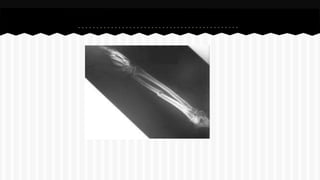

RESPONDA O NOME DO OSSO EM QUE

SE ENCONTRA A (S) FRATURA (A).